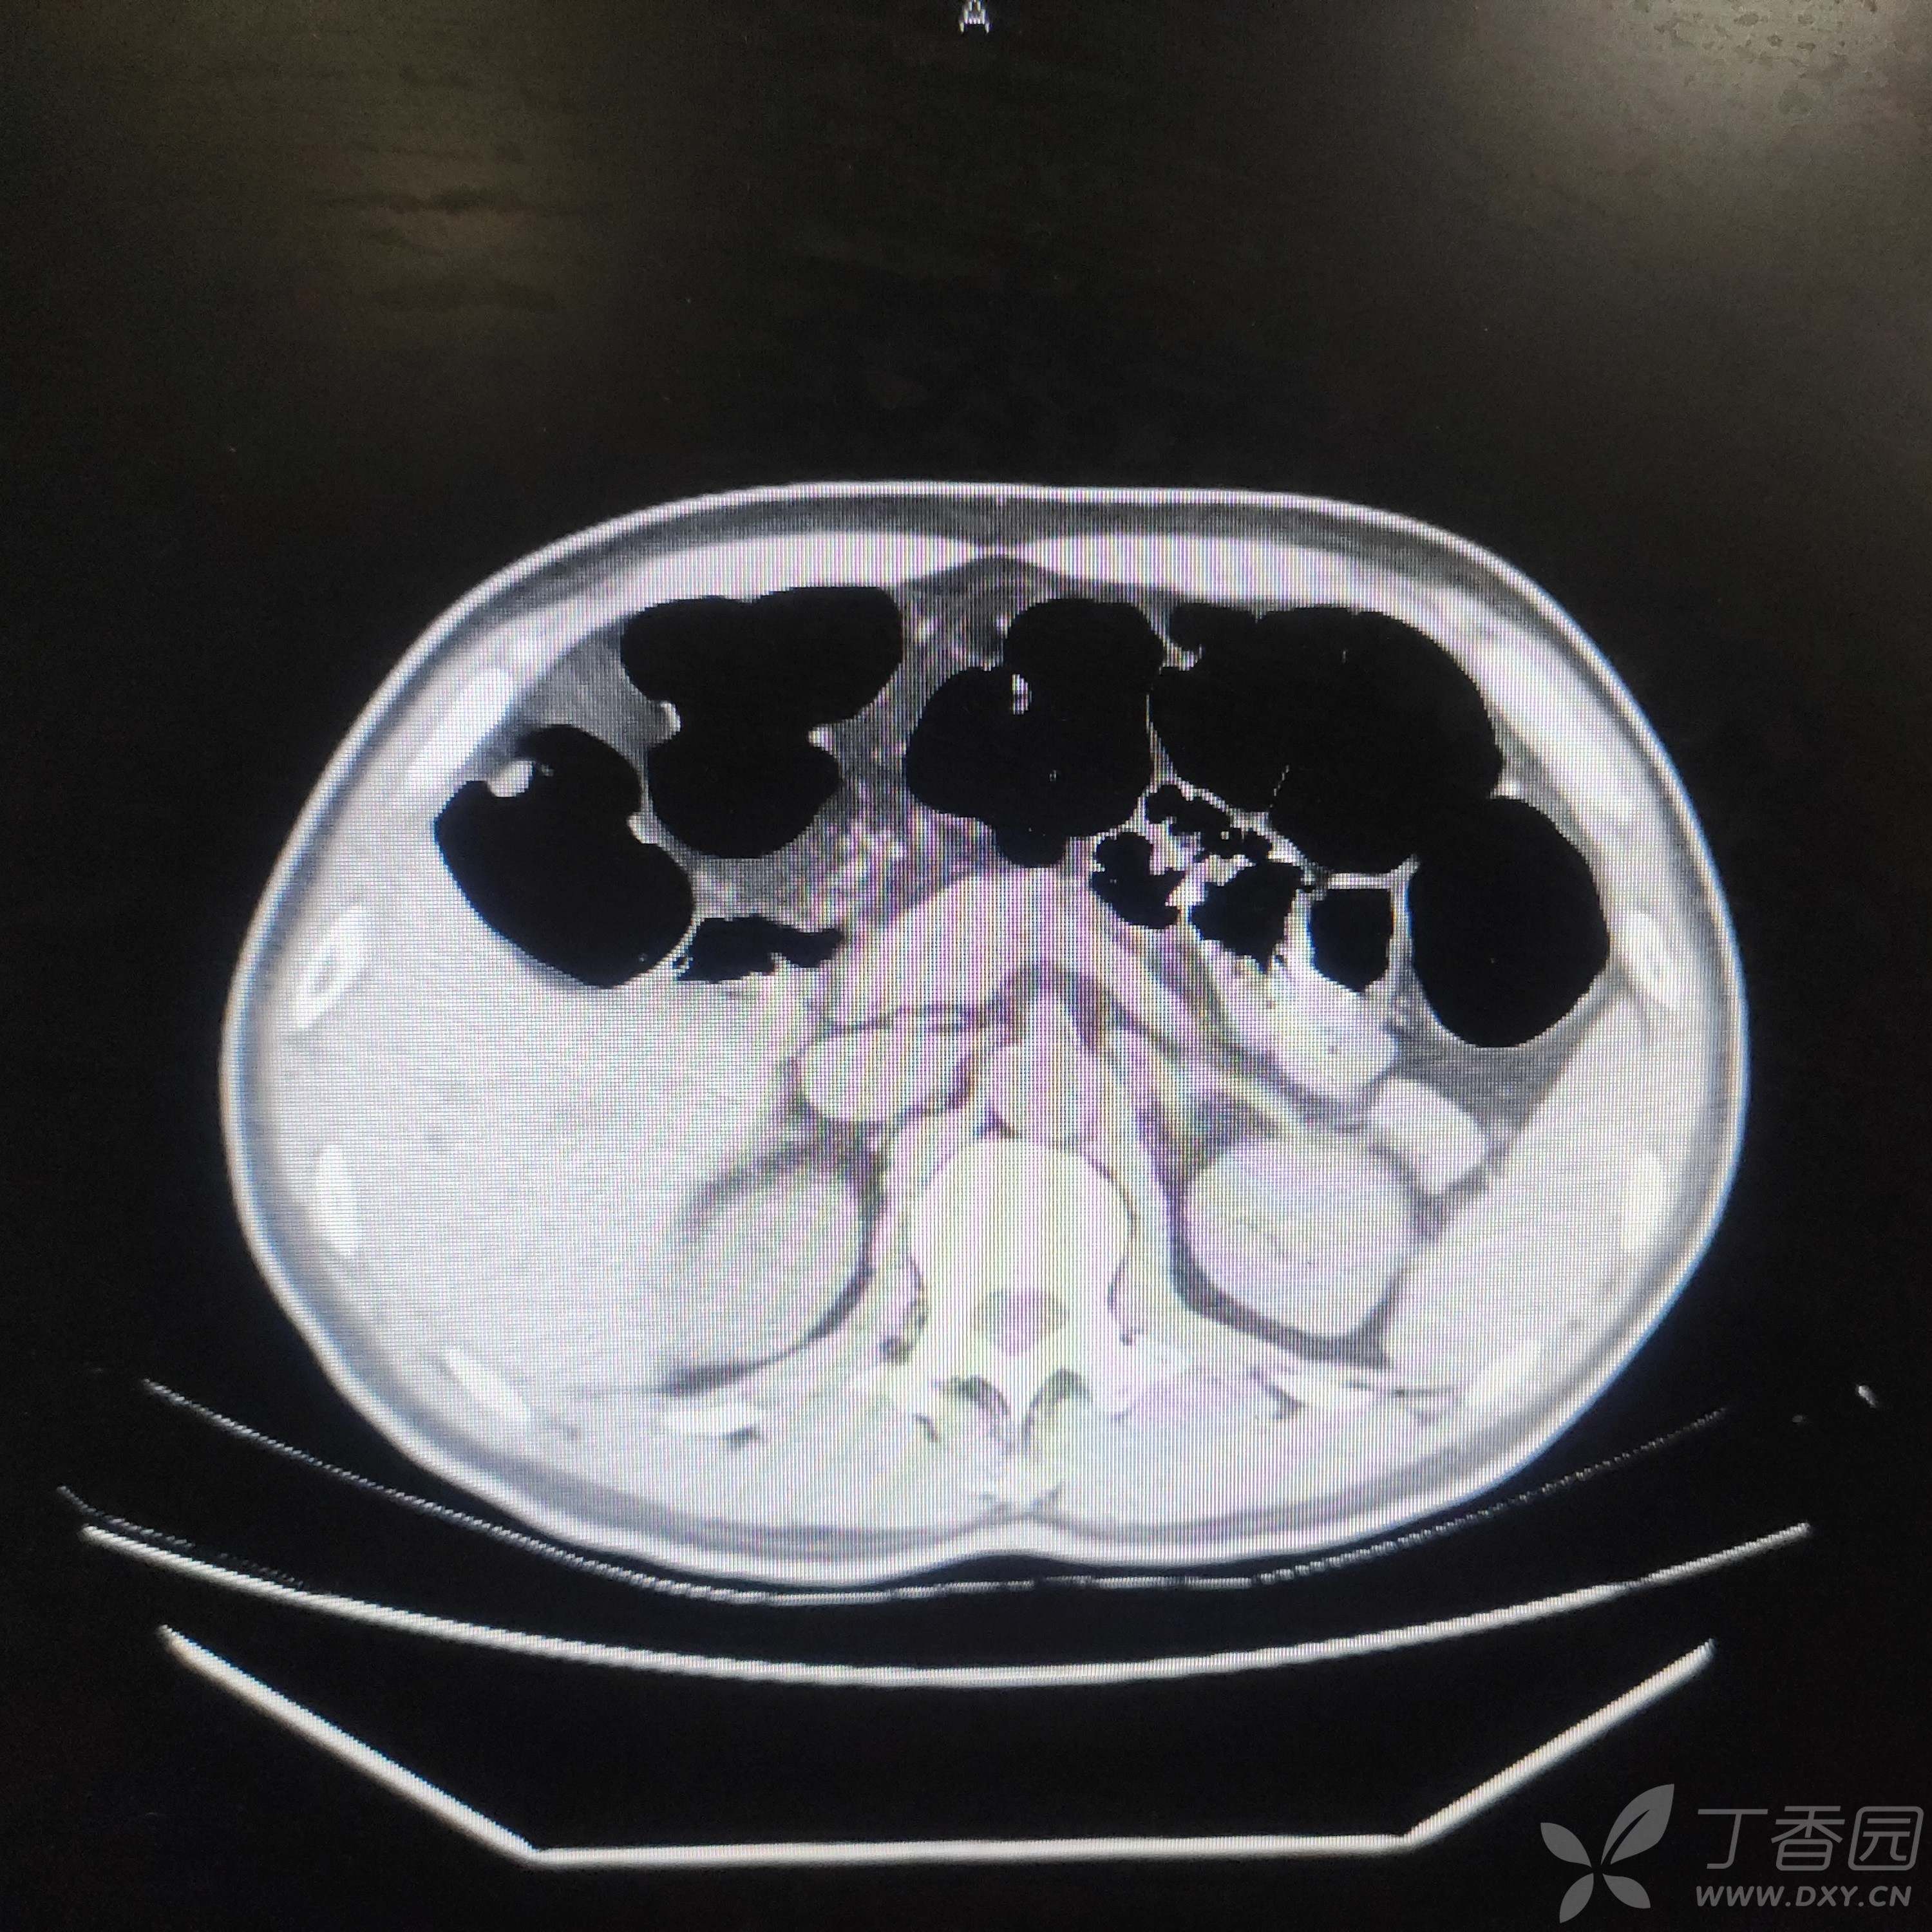

入院后血红蛋白进行性下降,正细胞性,1周内下降至74g/L,总胆29.7 umol/L,间胆22.5,CT肠管明显胀气(肠镜前空腹),未见占位,尿便常规、胃肠镜、胰腺增强MR、全腹盆腔CT未见责任病灶